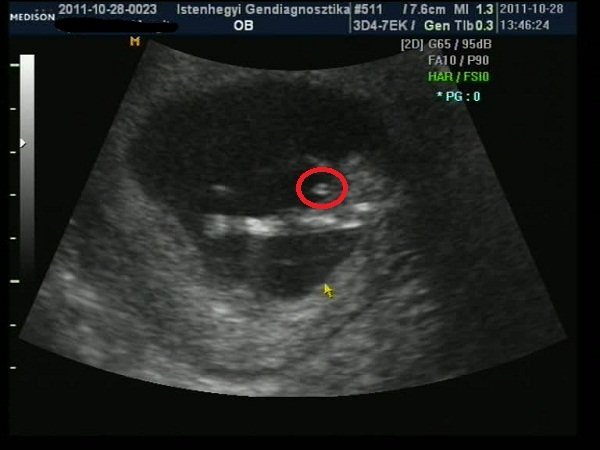

Nagyon jó volt az Istenhegyin, pikk-pakk levették a vért, aztán nem egészen egy óra múlva megvolt az uh, rettenetesen alapos volt a doki, 6-szor is megmérte a tarkóredőt (mert a határ határán volt, 2.4, és 2.5 felett szokott rezegni a léc, 3 felett rossz), aztán jól megnéztük mindenét, még 4D-ben is (sose voltam ilyenen:D), mindent elmagyarázott, végül kaptam egy dvd-t, és jó véreredményt kívánt.

– Akkor merek tippelni, mert nem fog haragudni, ha mégis tévedek. Szerintem kisfiú, és az ott egy kuki